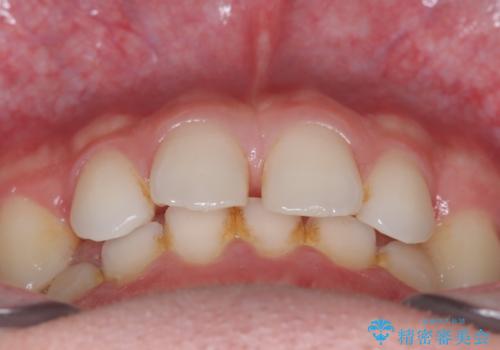

- 主訴:上の歯列の空隙を閉じたい

上顎前歯部に空隙が目立ちました。ワイヤー矯正、インビザライン(マウスピース矯正)どちらの方法でも適用症例と説明し、ワイヤー矯正治療(審美装置)を希望されました。